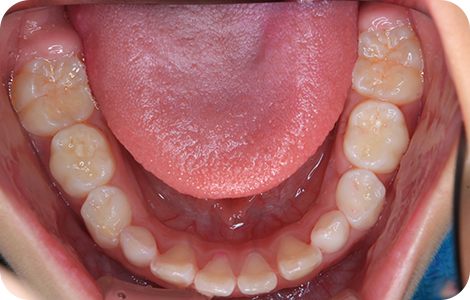

②子どもの矯正

BEFORE

AFTER

| 施術の説明 | 叢生を早期に改善する治療 |

|---|---|

| リスク・副作用 | 装置が入ることにより、虫歯のリスク、発音嚥下障害また一時的な顔貌の変化、正中の離開が起こります。 |

| 費用 | 462,000円 |

※税込表記です。